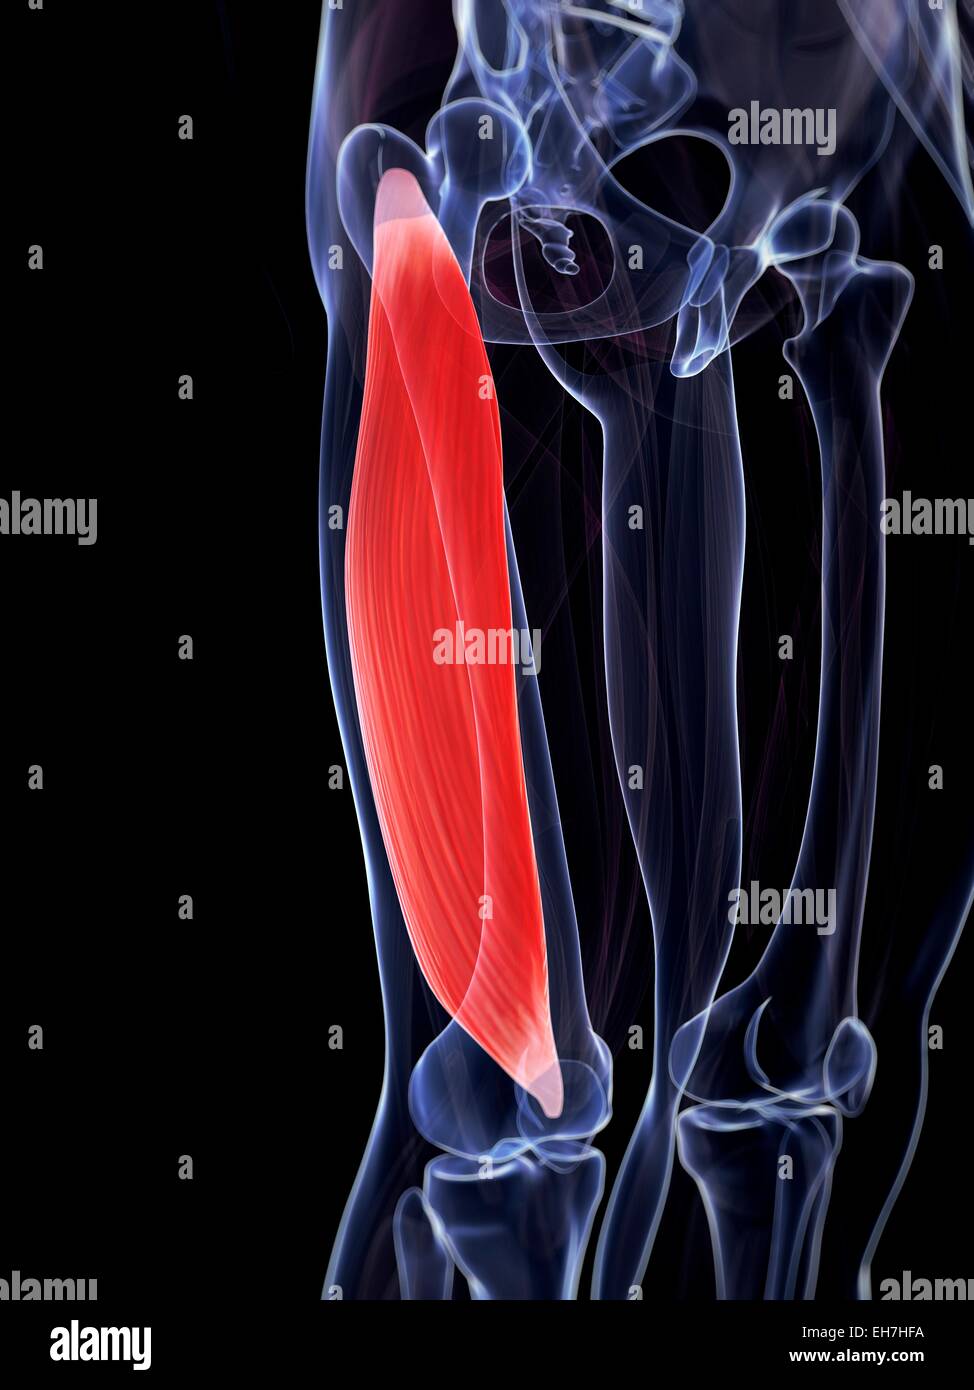

Les droits de la cuisse, illustration Banque D'Imageshttps://www.alamyimages.fr/image-license-details/?v=1https://www.alamyimages.fr/photo-image-les-droits-de-la-cuisse-illustration-79458046.html

Les droits de la cuisse, illustration Banque D'Imageshttps://www.alamyimages.fr/image-license-details/?v=1https://www.alamyimages.fr/photo-image-les-droits-de-la-cuisse-illustration-79458046.htmlRFEH7HFA–Les droits de la cuisse, illustration